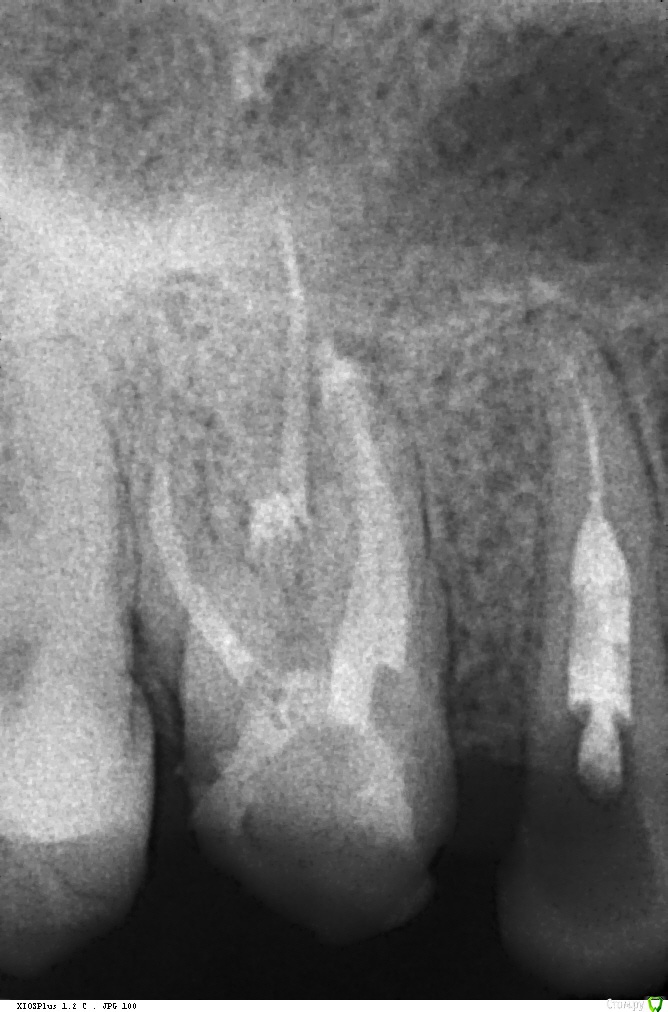

Весна2009 Опубликовано 30 января, 2017 Автор Поделиться Опубликовано 30 января, 2017 Снимок Ссылка на комментарий

Весна2009 Опубликовано 30 января, 2017 Автор Поделиться Опубликовано 30 января, 2017 Размер пришлось уменьшить,н е загружалось, качество стало хуже Ссылка на комментарий